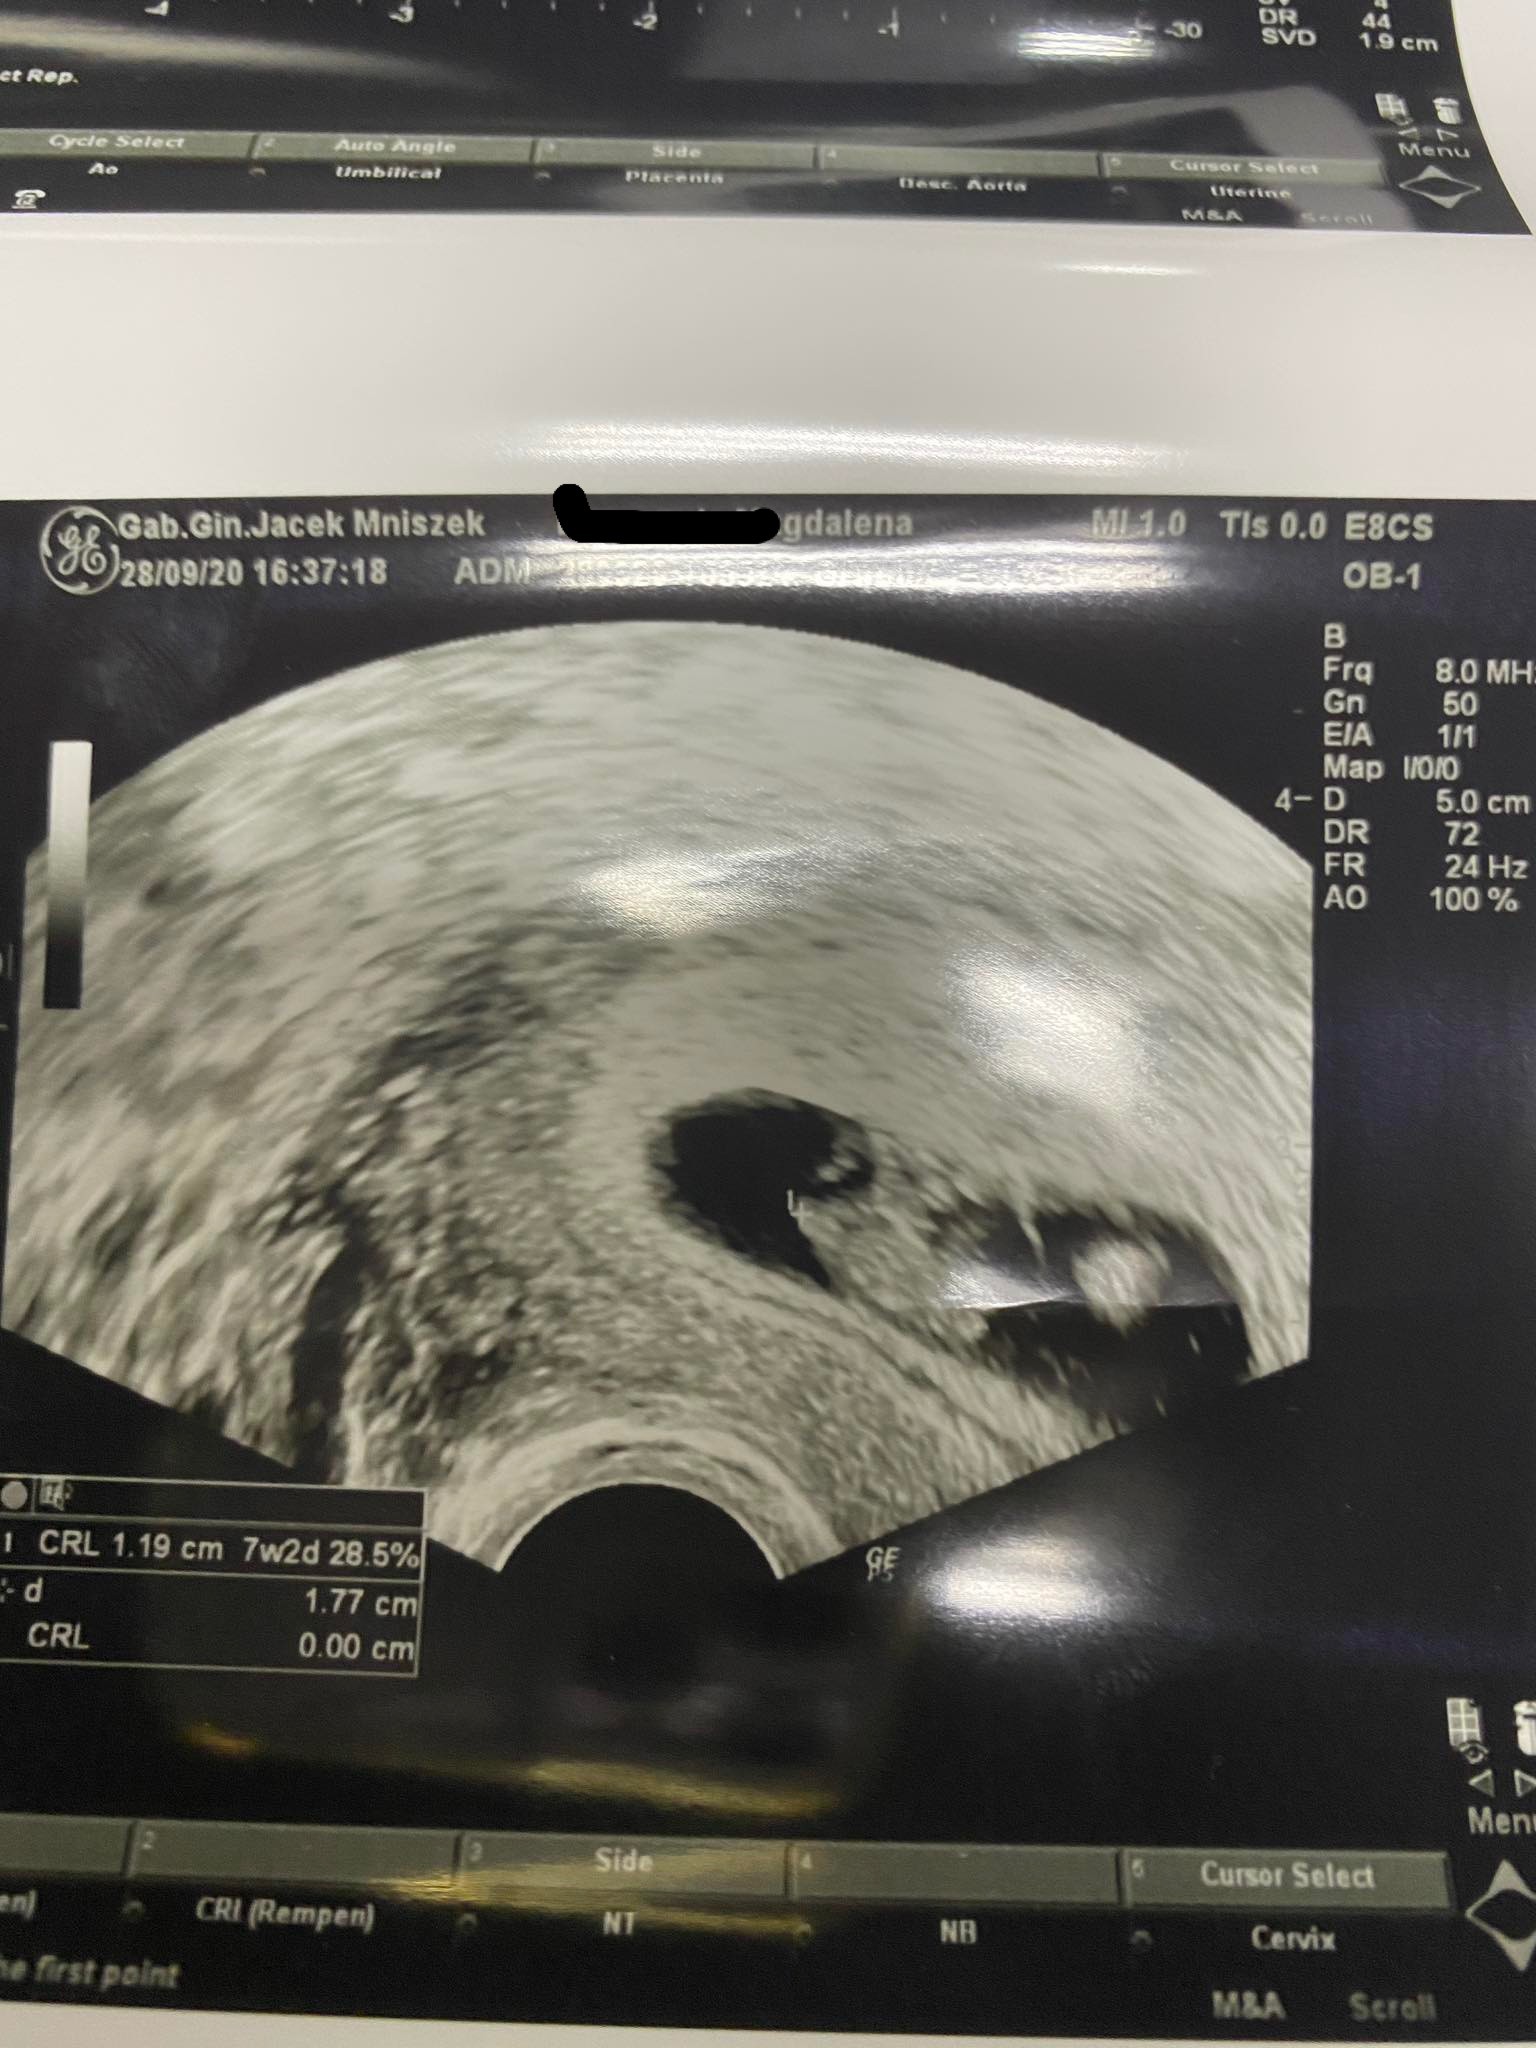

To superKochane Dziewczyny!ja tez po dzisiejszej wizycie jestem mega szczęśliwa - serduszko bije

Wszystko wygląda pięknie, 4mm szczęścia i wciąż rośnie!

z @ 7t 3d, a z USG 6t1d a przy moich długich cyklach - 35 i więcej dni jest to całkowicie w porzadku

kolejna wizyta za 4 tygodnie, 26.10. Zobaczymy ile mały Agent podrośnie do tego czasu, oby zdrowo!

Zobacz załącznik 1181707